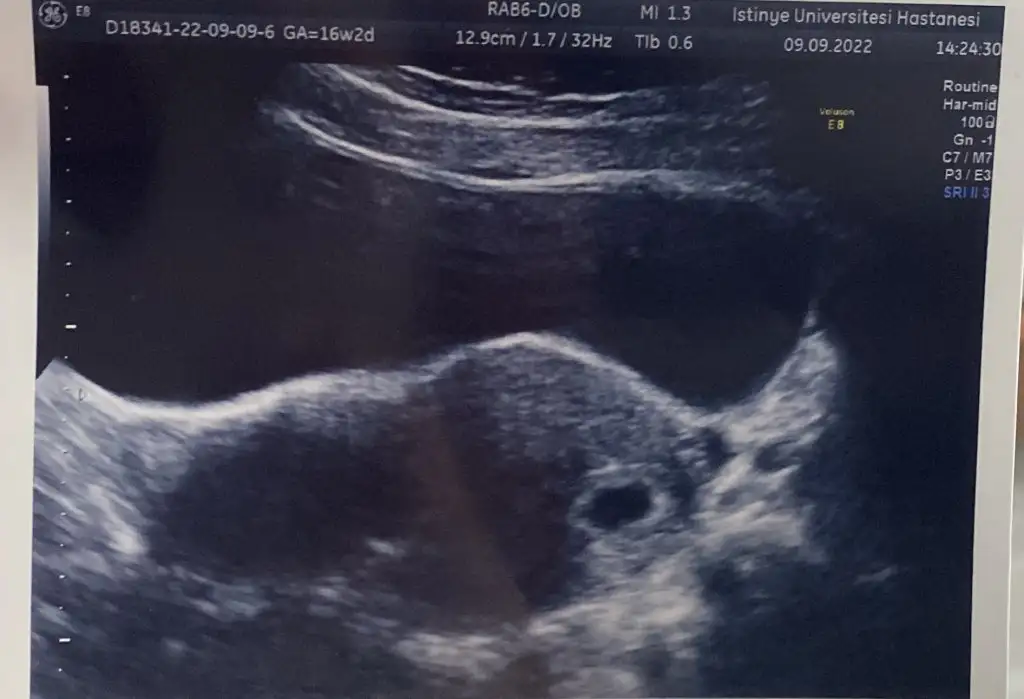

2022 Tüp Bebek Ağustos/Eylül Pozitif Görenler buraya :)

Kızlar siz keseyi görmeye gıttıgınızde bebegı ıcınde gordunuzmu

Bana doktorum suan bebek gorulmez zaten onu ancak kalpp. Atısıyla goruruz dedi

Karından yapılan 5 haftalık ultrasonda görünmüyor cnm. Vajinal olsaydı görünürdü diyr düşünüyorum. Benim doktorumda yolk filan demedi bazı doktorlar detaycıdır açıklar bazıları da gerekmedikçe bilgi vermez işte öğrendik bunu tecrübe ederek😅